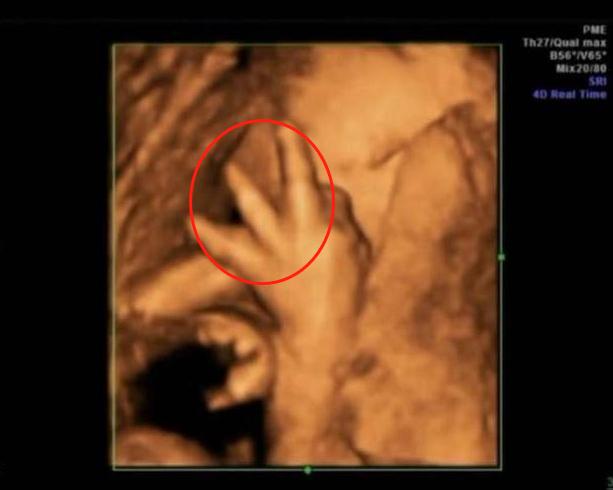

3.“捂鼻胎儿”火了,孕妈做四维彩超遭医生怒斥:真无知

前段时间,30岁的准妈咪小青去医院做四维胎超,当医生看到屏幕画面后,眉头紧锁,她们无法解释胎儿为何会做出如此奇怪的动作。

画面中,胎儿双手捂着鼻子,脸部表情十分痛苦,好似在与某种看不见的东西做抗争。

“我们过去从没见过这个姿势,不过这个姿势肯定不对劲,能和我们讲解下你的生活习惯吗?说不定可以找到答案。”